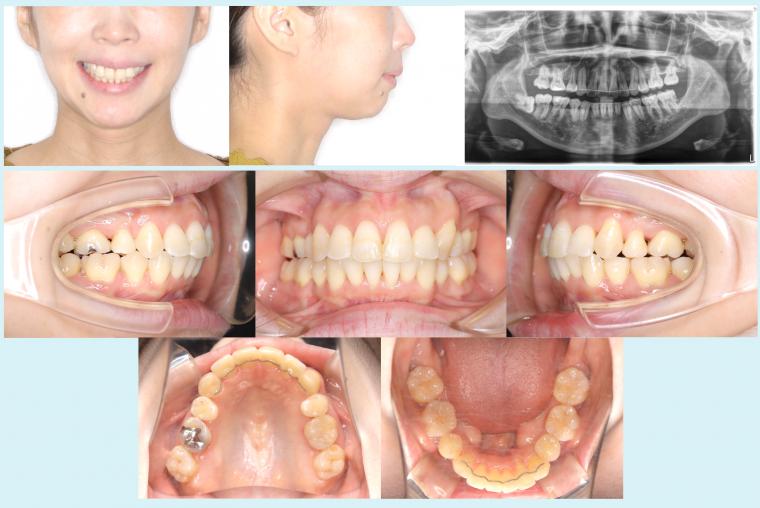

#47 アイステーションを使用した非対称症例